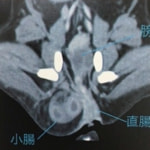

■症例5 11歳 未去勢雄 パピヨン

排便が困難になり始め、食欲が低下してきたとの主訴で来院。直腸検査にて直腸左側に宿便が貯留している憩室を認めた。

用手による摘便処置、緩下剤の内服と食餌療法をスタートしたが、排便困難が続いた為、会陰ヘルニア整復術実施に至った。

両側会陰ヘルニアを内閉鎖筋フラップ法にて整復し、直腸腹壁固定と去勢手術を同時に実施した。

術後、排便はスムーズになり食欲も安定し、経過は順調である。